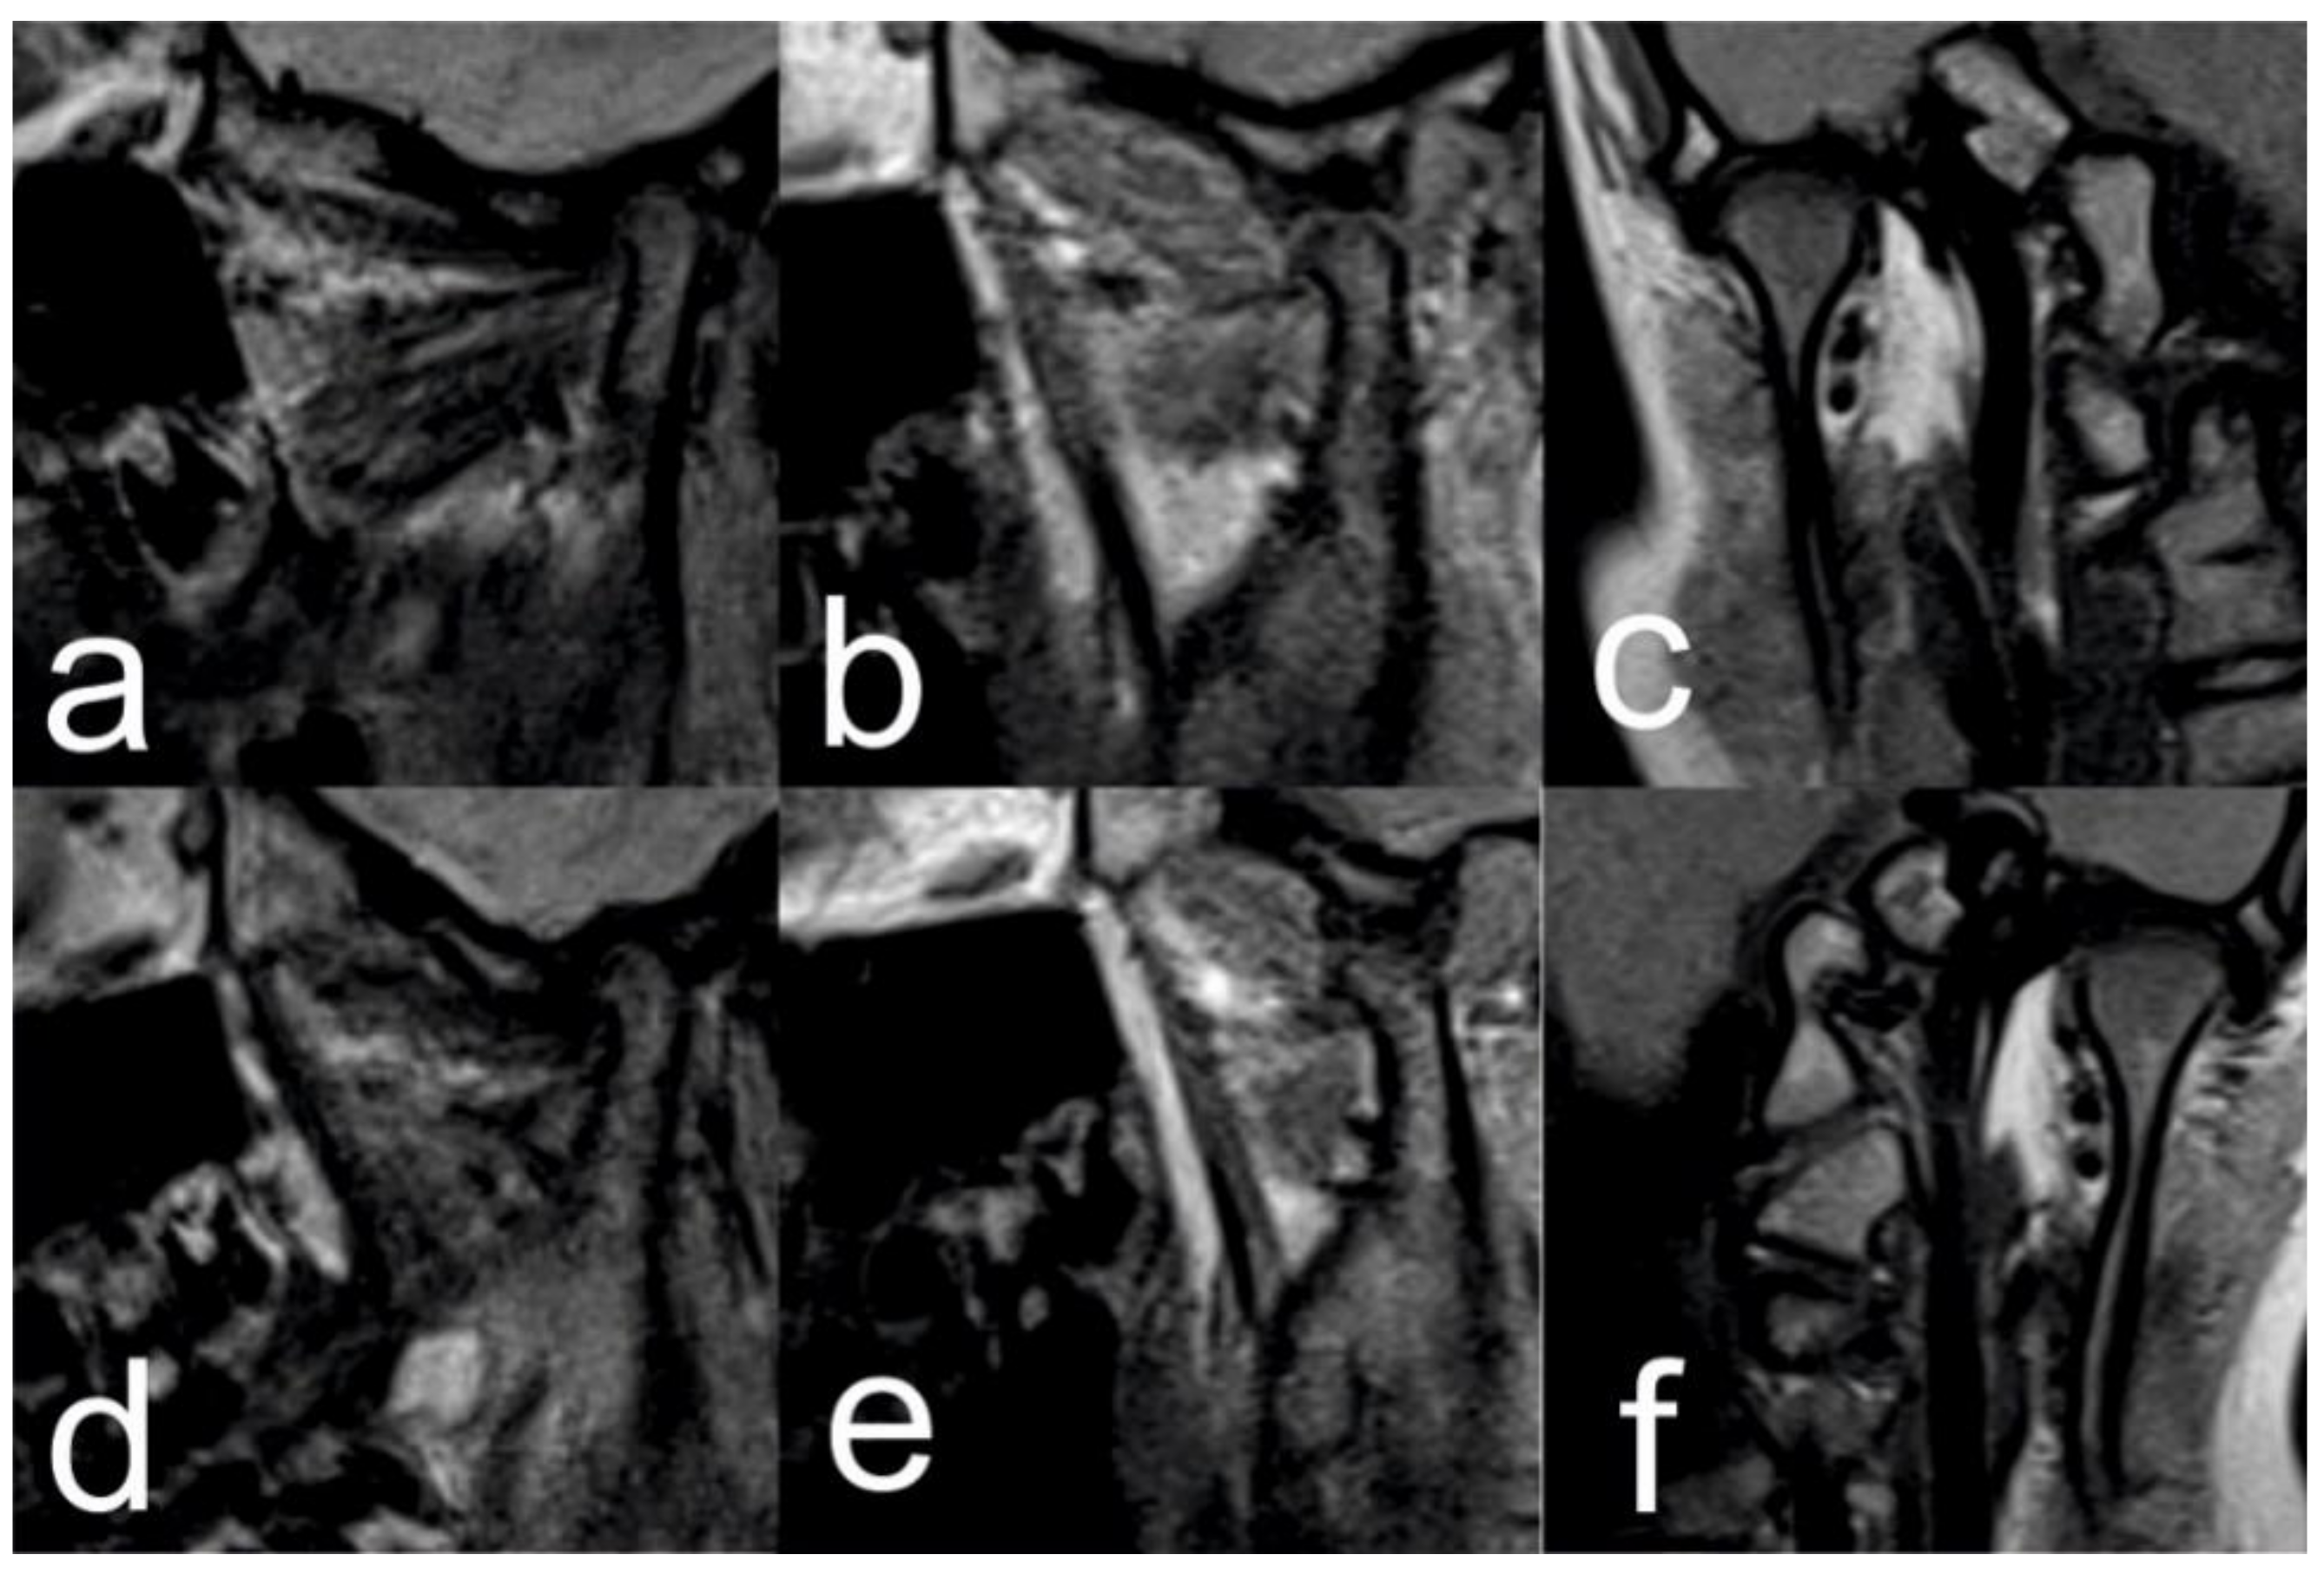

2.1. Initial Diagnosis and Initial Surgical Management

2.3. Treatment Progress